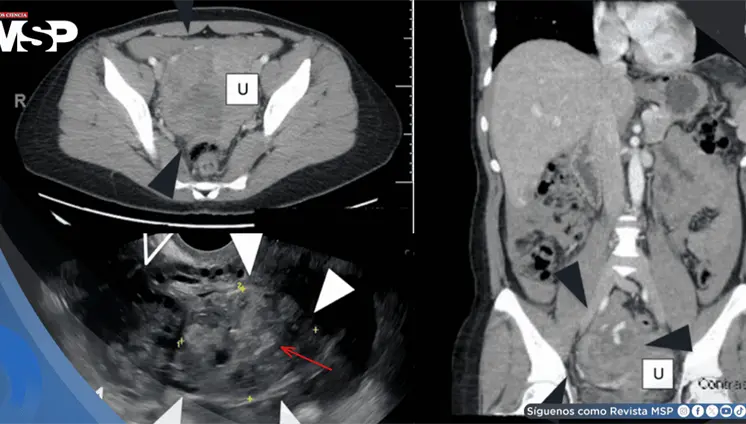

Lo que comenzó como un cuadro frecuente de dolor pélvico y dismenorrea en una mujer, terminó siendo un carcinoma folicular originado en estruma ovárico maligno. La paciente tenía solo 35 años, marcadores tumorales completamente normales y ninguna alteración tiroidea.

A pesar de los análisis normales, presentaba reserva ovárica baja y hallazgos ecográficos anormales. Durante la cirugía se descubrió daño severo en sus órganos reproductivos, con adherencias, trompas bloqueadas y destrucción del tejido ovárico.